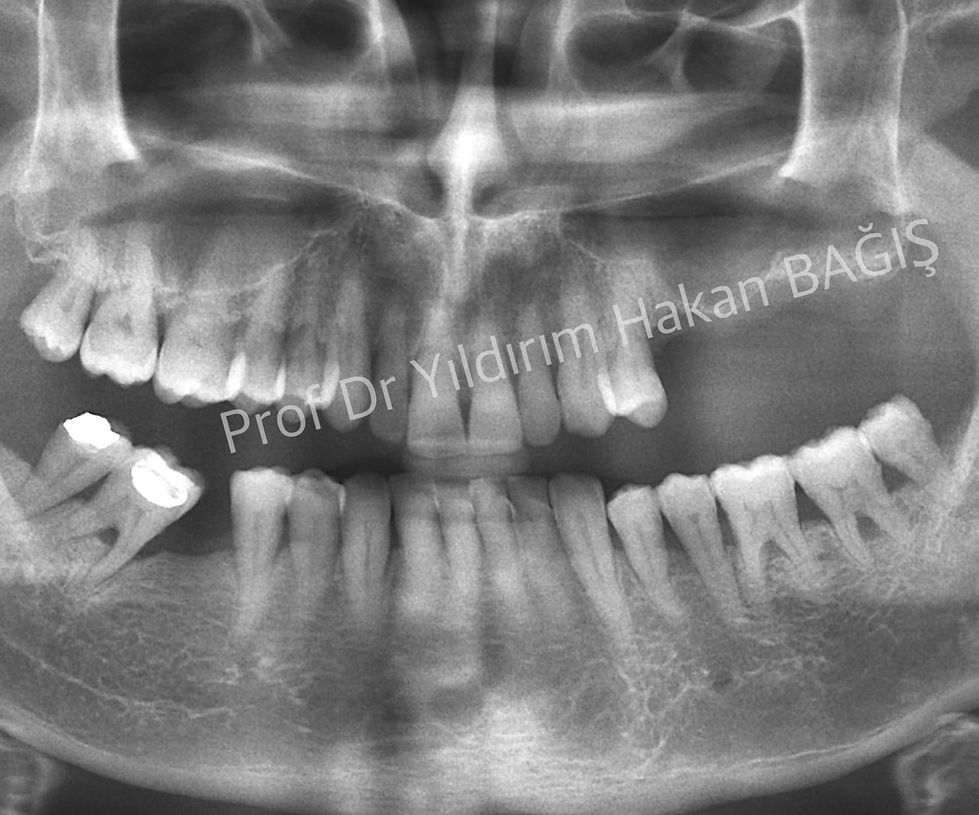

Üst çenede çiğneme alanlarında dişleriniz yok ve bu bölgede ağızda sabit kalan protezler istiyorsanız, tek çözümünüz implant uygulamalarıdır. Fakat, bazen üst çenedeki kemik istenilen kalınlıkta olmaya bilir. Bunun sebebi; adına, “maksiller sinus” denen kemiğin içindeki balon şeklindeki boşluktur. Sinüs Lifting veya sinüs yukarı alma bu balon şeklindeki boşluğun kemik benzeri bir madde ile doldurularak implant uygulamalarına hazır duruma getirilmesi işlemidir. Ne yazık ki, bu yöntem herkesin yapabileceği bir teknik değildir. Konusunda uzman kişilerin bile zorlanabileceği bir yöntemdir. Başarılı olmak ve üzerine diş yerleştirebilmek için günümüz şartlarında 6 ay beklenilmesi gerekir. Bazen operasyon başarısız olabilir ve maalesef hasta ve hekim yönünden olumsuzluklar olabilir. Mutlaka bu konular operasyon yapılmadan önce hastaya özenle anlatılmalıdır.